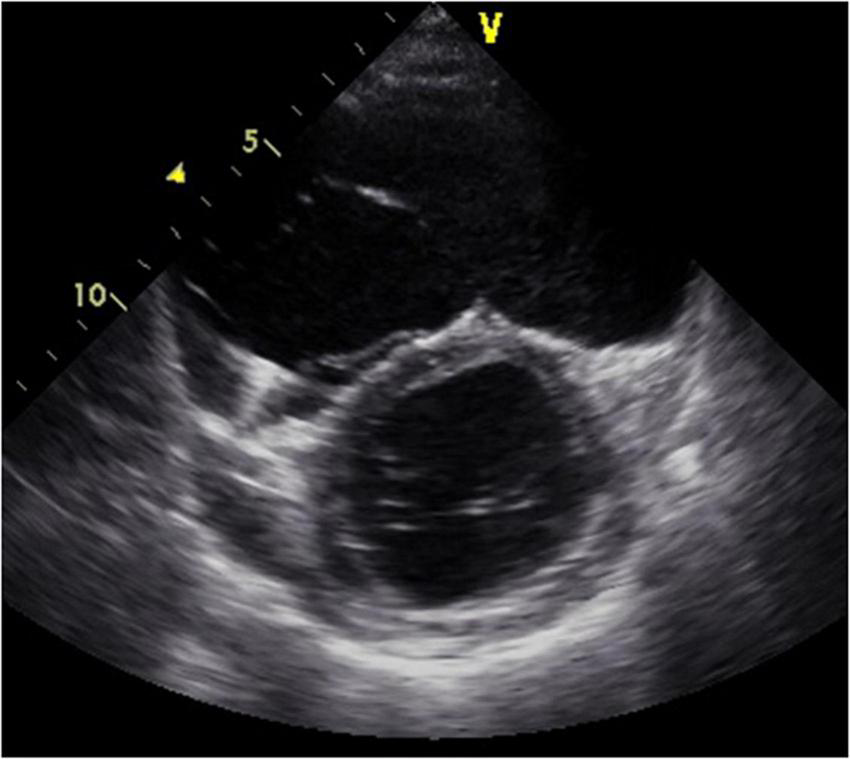

FIGURE 1

Short-axis view at end-diastolic phase of transthoracic echocardiography in Case 1. Note that the right ventricle is much larger than the left ventricle.